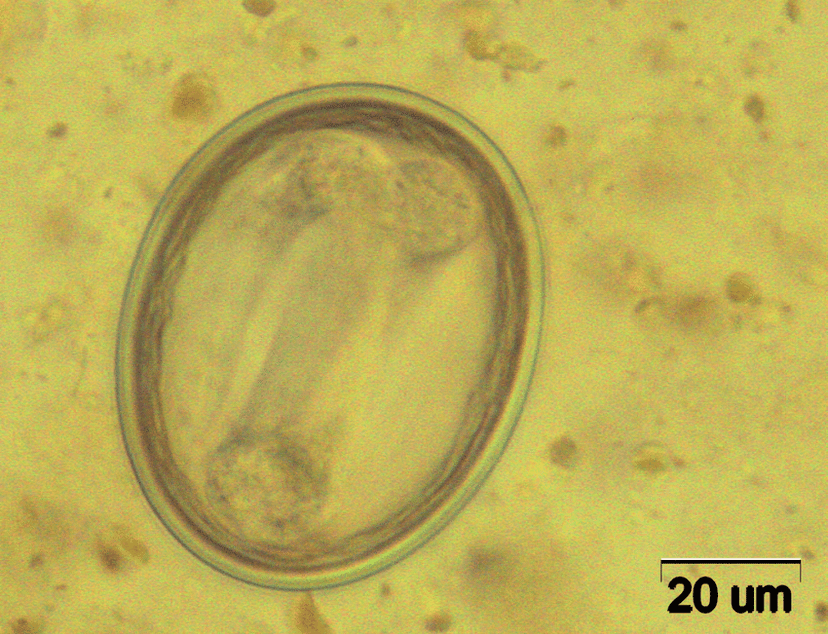

مشابه تخم توکسوکارا کانیس اما کوچکتر از آن، به ابعاد ۶۵*۷۵ میکرون هستند. فرورفتگی روی پوسته تخم ریزتر است.